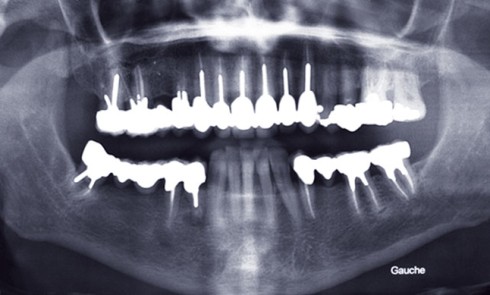

Article réservé à nos abonnés Esquisse d’un guide à la décision thérapeutique et au plan de traitement

La réhabilitation implantaire d’un site édenté ou en voie d’édentation peut se dérouler selon différents protocoles, tant chirurgicaux que prothétiques....